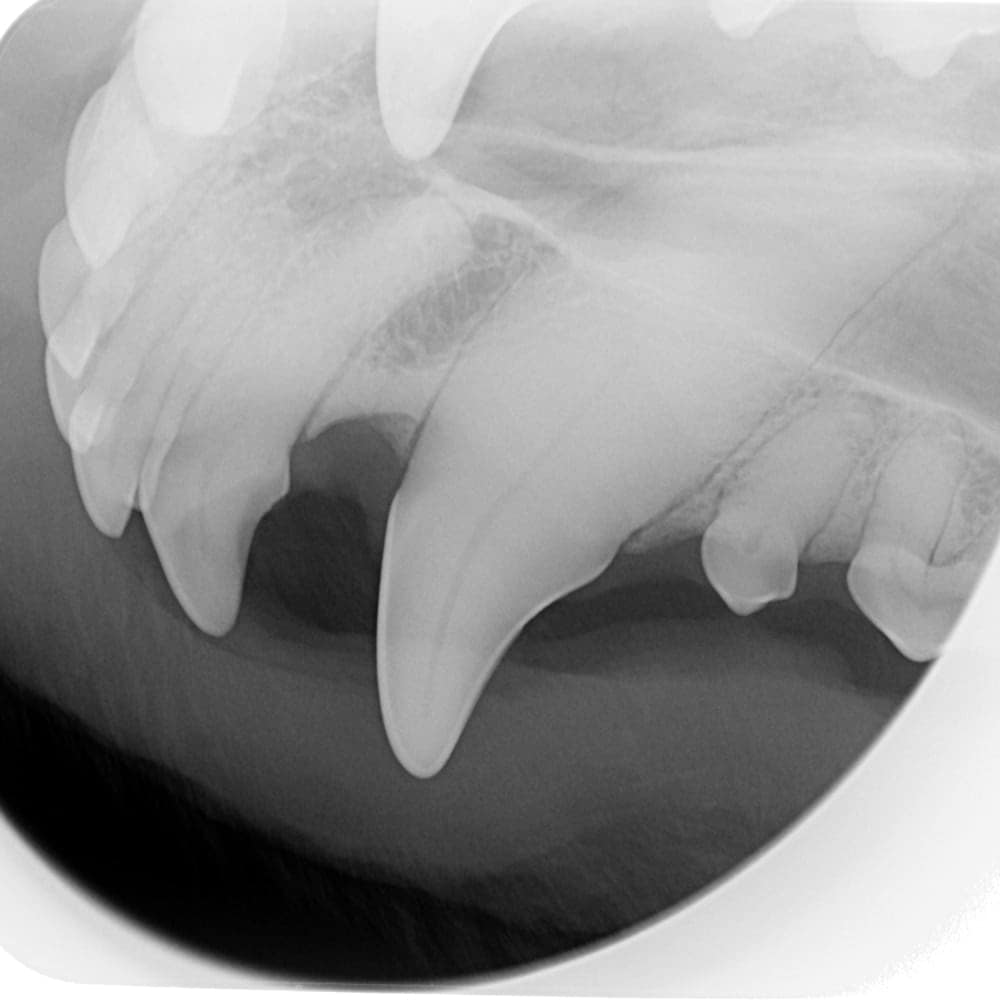

CR (Computed Radiography): The Indirect System

Indirect systems (indirect digital, computed radiography), or CR, use photostimulable phosphor plates to capture the image. These plates are available in several sizes (0, 1, 2, 3, 4, 5) and are about the thickness of a playing card.

These plates must be placed in protective plastic sleeves. Manufacturers recommend using a new sleeve for each EXPOSURE, although they can be reused a few times. Some brands of sleeves need to be torn in the center to be developed, making them unusable a second time. Although phosphor plates are less expensive than digital sensors (about $150 for a size 2 plate and $600 for a size 4), the cost of the sleeves must be considered. They can cost around $1 each, which increases operating expenses. On the other hand, it is less problematic if a patient bites the plate due to its more affordable price.

Phosphor plates can scratch more easily and delaminate if not cleaned with 99% alcohol. They must therefore be replaced after a few years, unlike digital sensors. The variety of sizes offered by this system is its main advantage: size 0 plates easily fit into the mouth of a 1 kg patient or a small cat. Size 4 plates are very useful for taking fewer shots on a large dog and provide a better overall view.

Sometimes, size 4 plates are used to X-ray small companion mammals – this type of system could be advantageous if you treat these kinds of patients in your clinic. Size 5 plates are sold by representatives but, in my humble opinion, offer little benefit in veterinary medicine. Two plates of sizes 0, 2, and 4 make a good kit for all patients.